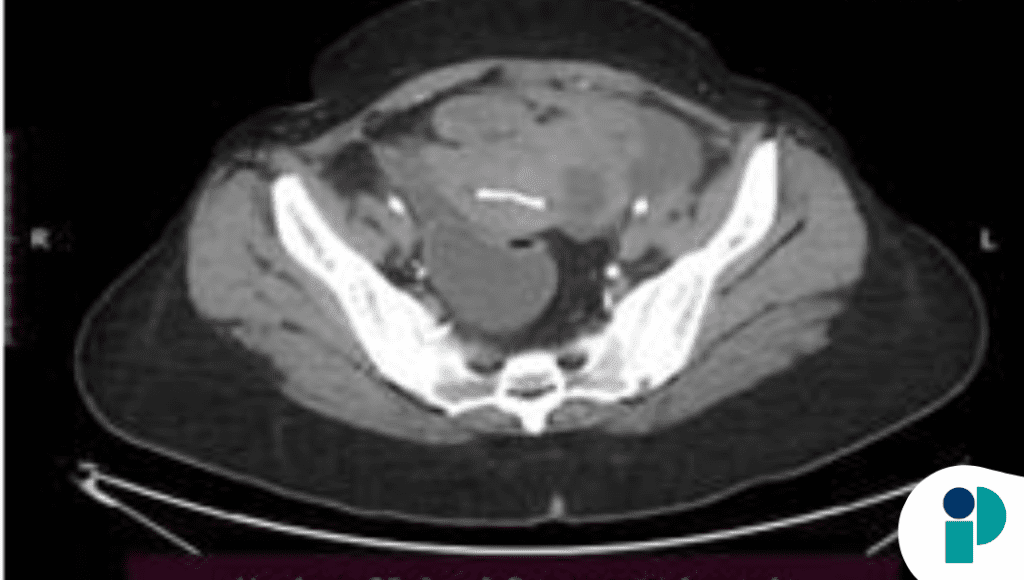

La tomografía computarizada con contraste reveló una masa compleja sugestiva de formación tumoral, colecciones abscesales en la cavidad, y perforación subcapsular del bazo, hallazgos que inicialmente llevaron a la sospecha de una neoplasia ovárica con metástasis hepática. Sin embargo, la evaluación intraoperatoria mostró adherencias densas, abscesos y perforación esplénica activa, lo que llevó a la splenectomía, evacuación de colecciones purulentas y biopsias de las lesiones.